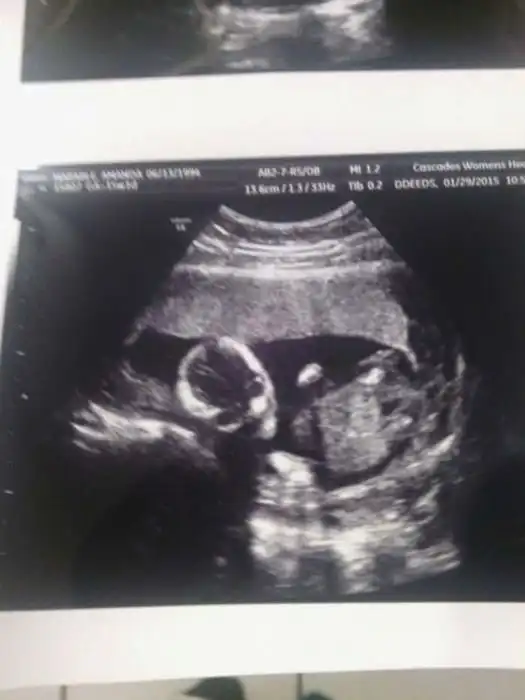

На экранах аппаратов УЗИ дети, находящиеся в утробе матери, выглядят далеко не такими милыми и симпатичными, какими они оказываются после своего рождения.